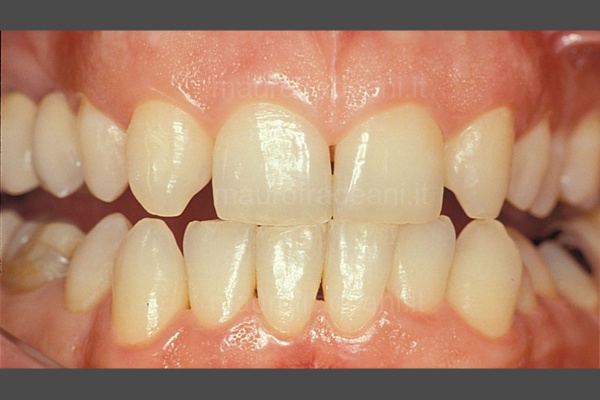

Oltre all’ortodonzia fissa con i classici “brackets”, negli ultimi anni si ricorre sempre più frequentemente all’ausilio di mascherine trasparenti, altrettanto efficaci ma esteticamente meno invasive.

L’impiego di tecniche di previsualizzazione del risultato finale quali il mock-up, oltre a facilitare al paziente la comprensione del piano di terapie proposto, gli permette addirittura di testare per qualche ora o per qualche giorno il nuovo sorriso. Preparazioni dentali minimali permettono la massima preservazione di struttura dentale e, in gran parte dei casi, evitano il ricorso alla somministrazione di anestesia.